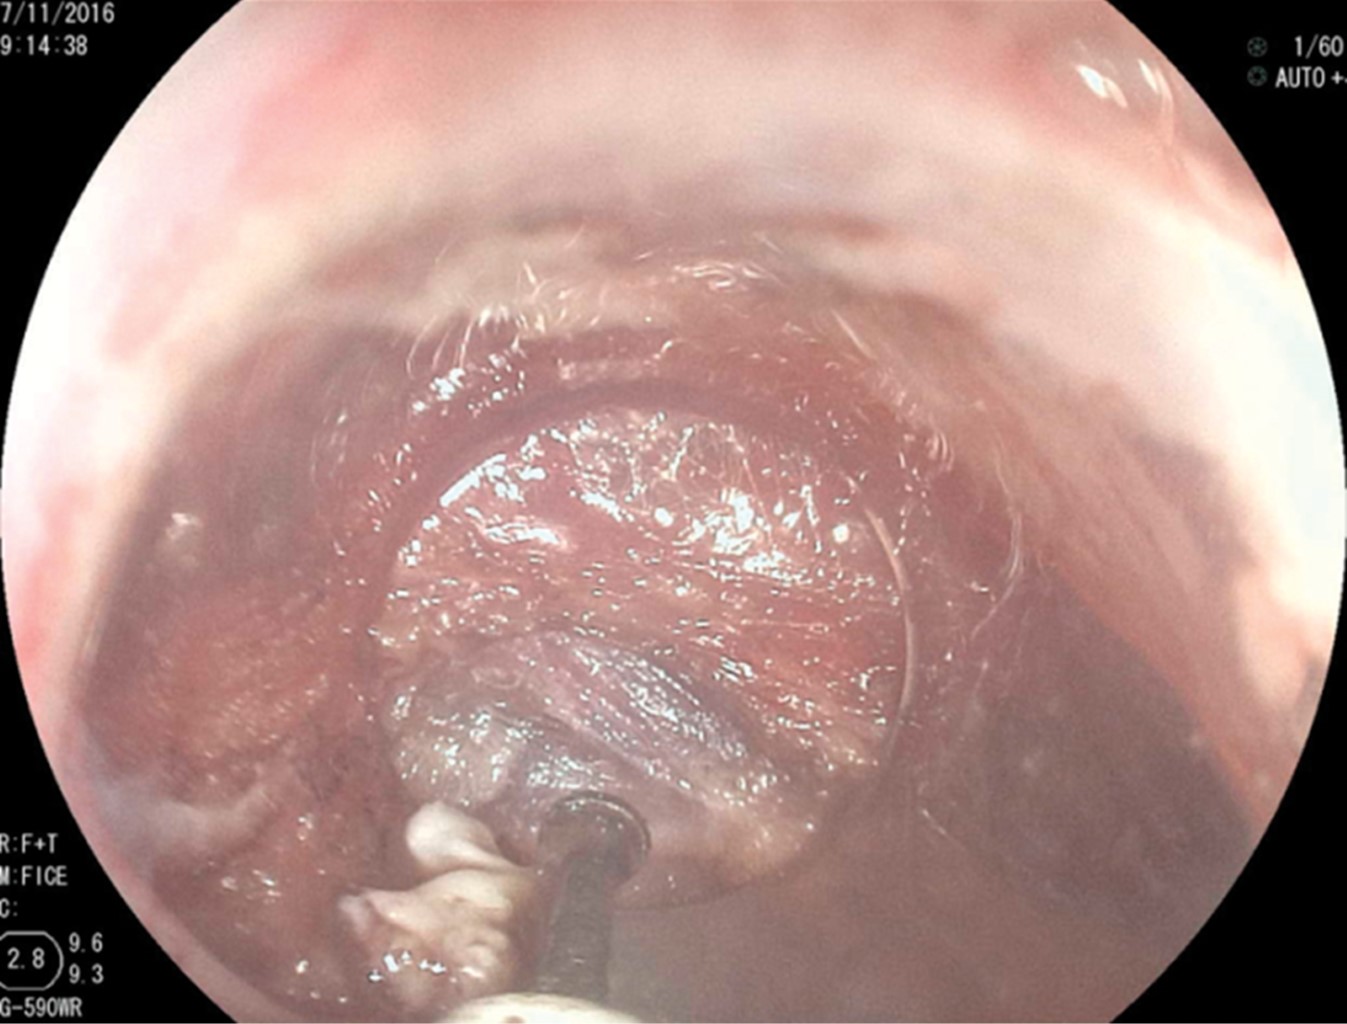

In the first 10 patients, once the esophageal lumen is identified, a metal guide is introduced and over it, a 7 mm or 21 Fr Savary-Gilliard dilator, which reaches the stomach and is left there. This adequately delimits the light of the diverticulum and esophagus (Figure 2). A clear plastic cap (MBL 6-1 Cook Endoscopy™) is placed at the distal end of the endoscope insertion tube and used as a spacer, which allows identification of the cricopharyngeal muscle septum. In the first 10 cases, an Olympus™ video gastroscope model GIF-H140 with an Olympus™ CV-140 image processor (Olympus Optical Co., Tokyo, Japan) of 9.8 mm diameter were used. Also, an Olympus UES-40 SurgMaster™ electrosurgical unit, and a needle knife (Needle Knife™, Cook Endoscopy, Winston-Salem, NC), were used. A cut was made in the edge of the esophageal light in the middle of the septum and towards the light of the diverticulum. First, the mucosa was cut exposing the cricopharyngeal muscle fibers (Figure 3). The cut was deepened until the section of the transverse fibers of the cricopharyngeal sphincter was completed, without necessarily reaching the bottom of the diverticulum (Figure 4), which allowed the edges of the mucosa incision to be brought closer together with metal clips, avoiding perforation and the risk of bleeding (Figure 5). The remaining four patients were treated with the POEM technique (Per Oral Endoscopic Myotomy), by infiltrating and lifting the submucosa with normal saline stained with methylene blue, then cutting the mucosa with the HybridKnife™ hydrodissector. The ERBE T-type™ is a multifunctional instrument that combines electrosurgical and waterjet technology in one. It lifts the mucosa and creates a submucosal tunnel, cutting only the transverse muscle fibers. Finally, the tunnel entrance was closed with endoscopic clips. In these patients, a Fujinon™ video gastroscope, Fujifilm Processor VP-4450HD™, ERBE VIO 200 D™ electrosurgical unit, and the ERBE HybridKnife, T-type™ with pure cutting and/or coagulation current (50 W) were used. Finally, the Savary-Gilliard dilator was removed. After the procedure, a swallow of water-soluble contrast material was given to rule out leakage. All patients were also given a single dose of antibiotics at the beginning of the procedure and were managed on an outpatient basis at home starting with a liquid diet after four hours.

Figure 4